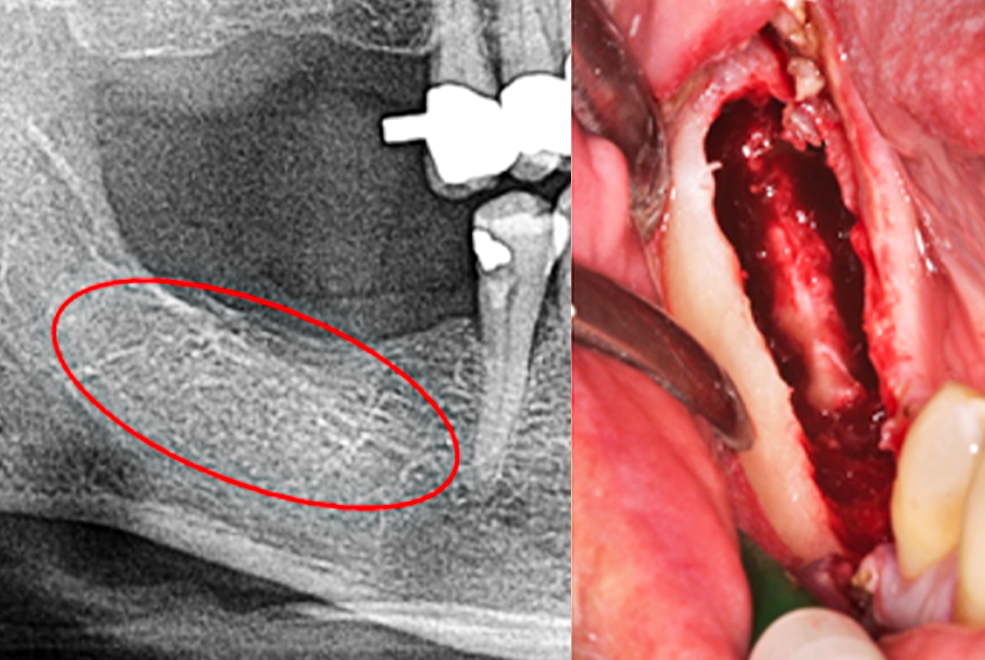

A central component in the development of the CaviTAU® device was the goal of locating possible cavities in the jawbone as precisely as possible in order to relieve patients from possible complications after or before upcoming operations.

The belief in the unlimited informative value of X-ray diagnostics is questioned and supplemented by the use of trans-alveolar ultrasound sonography (TAU with CaviTAU®).